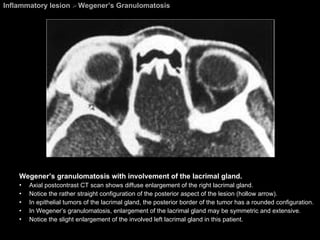

Wegener’s Granulomatosis Ocular involvement is also common: occurring in 18% to 50% of the cases. The disease  most commonly spreads from the paranasal sinuses to the orbit . The CT and MR imaging appearance ; Similar to that of  pseudotumor  and  lymphoma. Nasal and paranasal sinus involvement  is present in the majority of cases.

Inflammatory lesion  >  Wegener’s Granulomatosis Wegener’s granulomatosis with involvement of the lacrimal gland.  Axial postcontrast CT scan shows diffuse enlargement of the right lacrimal gland.  Notice the rather straight configuration of the posterior aspect of the lesion (hollow arrow). In epithelial tumors of the lacrimal gland, the posterior border of the tumor has a rounded configuration. In Wegener’s granulomatosis, enlargement of the lacrimal gland may be symmetric and extensive.  Notice the slight enlargement of the involved left lacrimal gland in this patient.